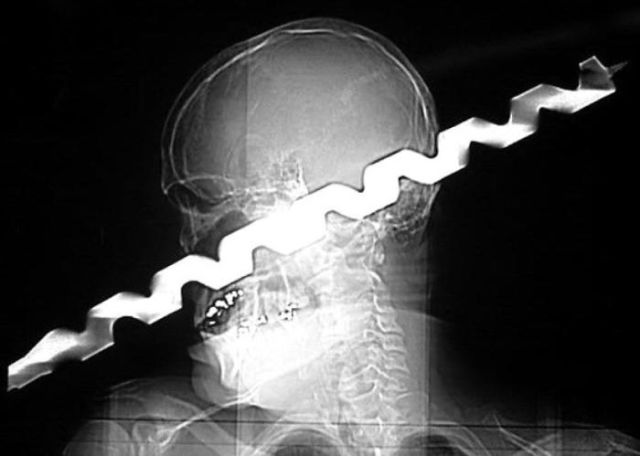

These x-rays will make you wonder how this could ever have happened in the first place.